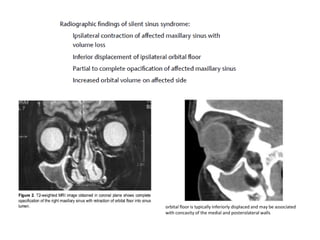

SILENT SINUS SYNDROME

First case of maxillary sinus opacification and collapse

was reported by Montgomery.

Term “silent sinus syndrome” (SSS) for this phenomenon

was coined by Soparkar et al. in 1994

Pathogenesis of SSS is based on chronic maxillary sinus

obstruction related to occlusion of the maxillary

infundibulum, which results in a hypoventilated sinus and

negative pressures within the sinus

Choudhary SH, Kale L, Mishra SS, Choudhary AK. Silent sinus syndrome: An

imploding antrum syndrome. J Indian Acad Oral Med Radiol 2016;28:30-3

FEATURES:-

“sinking down of the eye” or

“drooping of the upper eyelid”

a) Enophthalmos and hypoglobus of right eye

(black arrow)

b) deepening of left superior orbital sulcus

orbital floor is typically inferiorly displaced and may be associated

with concavity of the medial and posterolateral walls

MANAGEMENT

Treatment for SSS is mostly surgical with otolaryngological

intervention.

1) surgical treatment was done by performing a Caldwell–

Luc procedure and transconjunctival repair of the orbital

floor.

2) Blackwell et al. in 1993 endoscopic maxillary antrostomy

in conjunction with a transconjunctival orbital floor repair,

having a greater success rate.